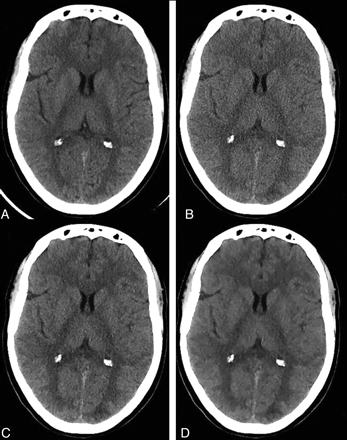

Examples of nonenhanced head CT images of an adult patient obtained at a regular dose without ASIR (A), a lower dose without ASIR (B), and a lower dose with 60% (C) and 100% (D) of ASIR.

There was a significant decrease in image noise and scatter-related artifacts when applying 60% and 100% ASIR in the lower-dose group in comparison with the regular- and lower-dose groups without ASIR (P < .0001). A statistically significant increase in GM-WM differentiation was noted when using ASIR levels of 60% and 100% in the lower-dose group in comparison with the regular dose and lower-dose groups without ASIR (P < .0001) (Fig 4). The image-quality indices in the routine higher-dose group (175 mAs) were not significantly different from similar indices from scans acquired at 140 mAs (reduced-dose group) with an ASIR level of 30%.

Regarding the visibility of small anatomic structures and image sharpness, there was no statistically significant difference between the lower- (independent of ASIR level) and regular-dose groups (Table 5).